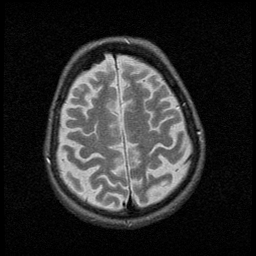

Huntington's Chorea, MR -- Slice #16

[Home][Help][Clinical] Slice 16